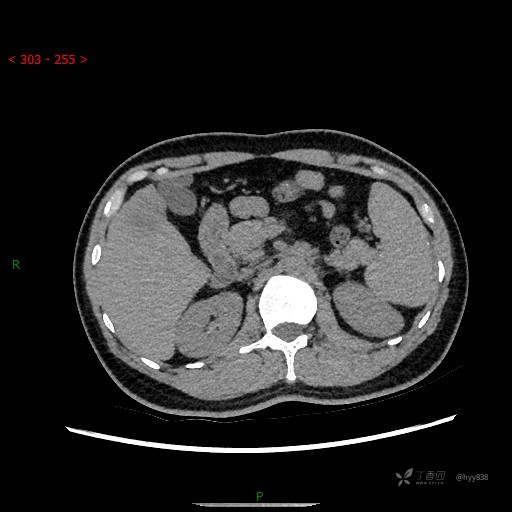

延迟期